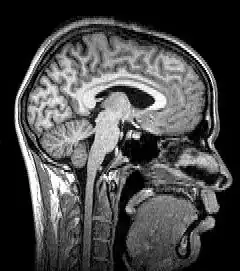

Neuroimagem ou imagem cerebral é o uso de várias técnicas para imagem, direta ou indiretamente, da estrutura, função/farmacologia do sistema nervoso. Essa é uma disciplina relativamente nova dentro da medicina, neurociência e psicologia.[1] Os médicos que se especializam no desempenho e na interpretação da neuroimagem no cenário clínico são denominados neuroradiologistas.

Imagem de ressonância magnética

A ressonância magnética (MRI) usa campos magnéticos e ondas de rádio para produzir imagens de duas ou três dimensões de estruturas cerebrais de alta qualidade sem uso de radiação ionizante (raios-X) ou traçadores radioativos.